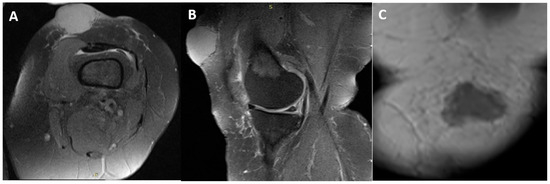

Merkel Cell Carcinoma of the Thigh Presenting as a Hemorrhagic Mass: A Rare Case Report and Literature Review

by Hüseyin Emre Tepedelenlioğlu, Özlem Orhan, Şefik Murat Arıkan and Güldal Esendağlı

Curr. Oncol. 2026, 33(4), 204; https://doi.org/10.3390/curroncol33040204 - 1 Apr 2026

Background: Merkel cell carcinoma (MCC) is a rare, aggressive primary cutaneous neuroendocrine carcinoma with a marked propensity for early regional lymph node metastasis. Although MCC most often arises on sun-exposed head and neck skin in older adults, tumors of the lower extremity are uncommon and may be mistaken for benign hemorrhagic lesions. Case presentation: A 54-year-old woman developed a rapidly enlarging, hemorrhagic mass in the left suprapatellar thigh. Magnetic resonance imaging demonstrated an extracompartmental subcutaneous soft-tissue mass without quadriceps muscle invasion. Wide local excision including the quadriceps fascia was performed. Histopathologic examination showed a dermal/subcutaneous small blue round cell neoplasm with brisk mitotic activity. Immunohistochemistry demonstrated diffuse cytoplasmic synaptophysin positivity, paranuclear dot-like CK20 reactivity, chromogranin A positivity, and negative MCPyV staining; TTF-1, S100, melan-A, HMB-45, and hematolymphoid markers were negative. Staging positron emission tomography/computed tomography identified ipsilateral inguinal nodal involvement. Therapeutic inguinal lymph node dissection revealed metastatic MCC in one of four lymph nodes without extranodal extension. The final stage was pT3 pN1b cM0 (AJCC 8th edition), corresponding to stage IIIB disease. Adjuvant radiotherapy (57 Gy in 20 fractions) was delivered to the primary bed and ipsilateral inguinal basin. The patient remains disease-free at 5-year follow-up. Conclusions: Lower-extremity MCC can mimic hemorrhagic or post-traumatic lesions, contributing to diagnostic delay. Persistent or rapidly enlarging “hematoma-like” lesions warrant early biopsy, and timely pathologic nodal staging is essential. Multimodal management can achieve durable control even in node-positive disease Full article

(This article belongs to the Section Dermato-Oncology)

Show Figures

Figure 1